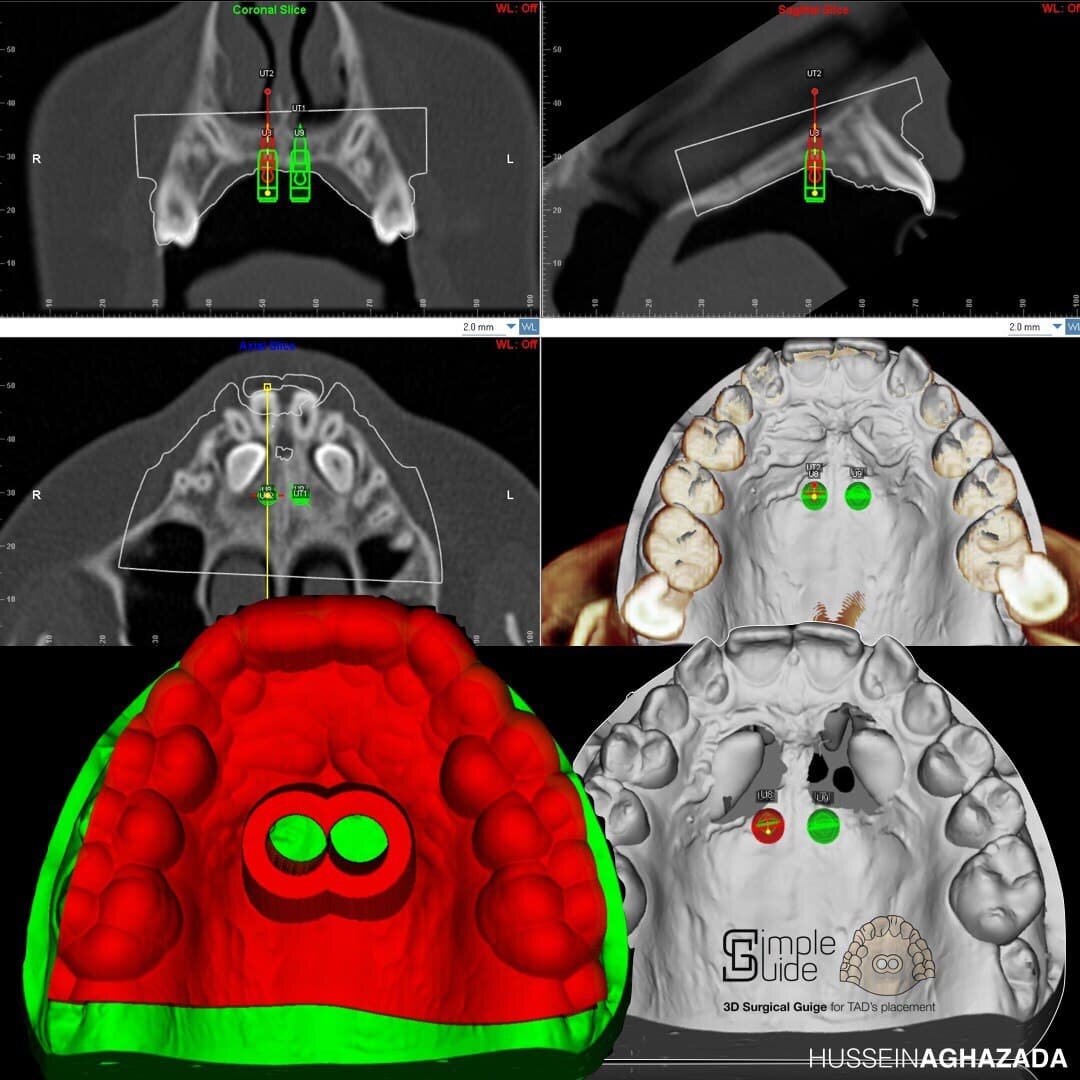

Это минивинты, которые будут использоваться как опора для аппарата расширения

Коротко это выглядит так: делаем оптический слепок рта внутриротовым сканером изнутри, накладываем поверх этого данные КТ, загоняем в аналог Архикада для ортодонтов (Dolphin), совмещаем, рассчитываем оптимальное место для имплантов — мини-винтов, печатаем навигационный шаблон из пластика и выпекаем лазером аппарат, потом вставляем одно в другое, потом вкручиваем это в пациента и радуемся. Получается идеальная точность. А это, знаете ли, важно, когда вы решаете взять и раздвинуть кости черепа ребёнку.